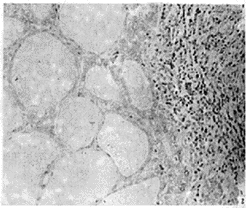

靜止性淋巴細胞性甲狀腺炎活檢發現像橋本甲狀腺炎一樣的淋巴細胞浸潤,但無淋巴濾泡和瘢痕。妊娠期和產後期甲狀腺過氧化酶抗體和少見有抗甲狀腺球蛋白抗體幾乎總是陽性,因此該病是橋本甲狀腺炎的變異型(見下文)。靜止淋巴細胞性甲狀腺炎血清T3 ,T 4 水平增高,TSH抑制伴極低放射性碘吸取,這些實驗室檢查類似亞急性甲狀腺炎,人為甲狀腺功能亢進和碘誘導甲狀腺功能亢進所見。白血球計數和血沉正常,無眼征和脛前粘液性水腫。

靜止性淋巴細胞性甲狀腺炎2、橋本甲狀腺炎:由於自身免疫因子引起腺體淋巴細胞浸潤的慢性甲狀腺發炎.組織學研究發現甲狀腺廣泛淋巴細胞浸潤伴有淋巴濾泡。

影像圖2.甲狀腺穿刺活檢:細針穿刺見有大量淋巴細胞、漿細胞,可有嗜酸性變的瀘泡細胞出現。